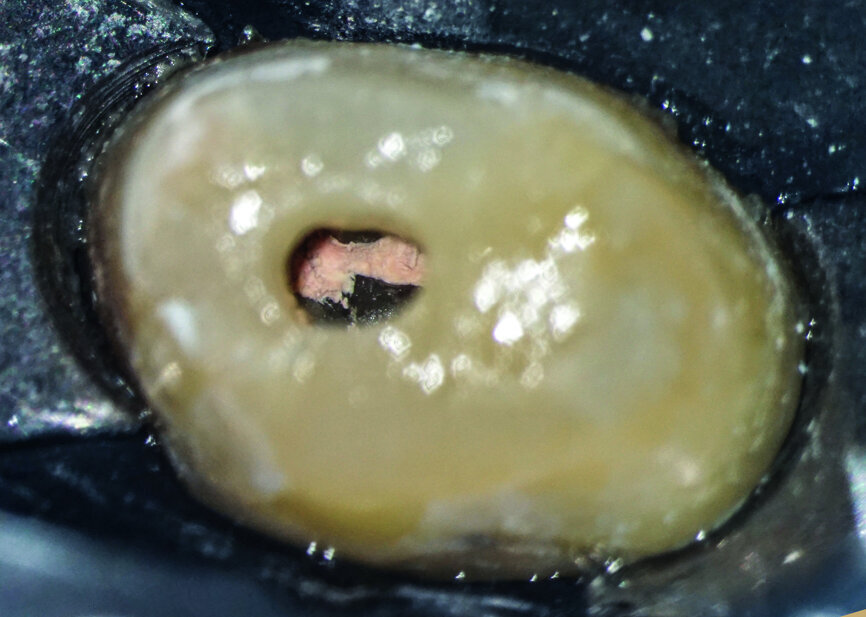

After isolation of the tooth (Fig. 3), an access cavity was created using high-speed diamond burs and ultrasonic tips (Figs. 4–8). Pre-flaring in the coronal and middle thirds was done with the HyFlex EDM 25 instrument (at a torque of 4 Ncm and a speed of 500 rpm). It is a proven fact that pre-flaring allows an increase in the instrument size that binds in the root canal, irrespective of the discrepancy between the size of the file and anatomical diameter. [19–21] Afterwards, canal scouting was performed using an ISO size 10 stainless-steel K-file up to working length. Upon establishing the working length, with the help of an apex locator, the 10/05 EDM file (glide path file) was used up to working length (at a torque of 3 Ncm and a speed of 300 rpm). Subsequently before finishing the preparation with the 25 EDM file, the 20/05 EDM (preparation file) was used to full working length (at a torque of 3 Ncm and a speed of 400 rpm). At this point, the working length was confirmed again with an ISO size 20 NiTi K-file. Root canal shaping was completed with the 25 EDM file, which was inserted to full working length (at a torque of 3 Ncm and a speed of 400 rpm; Figs. 9–12).